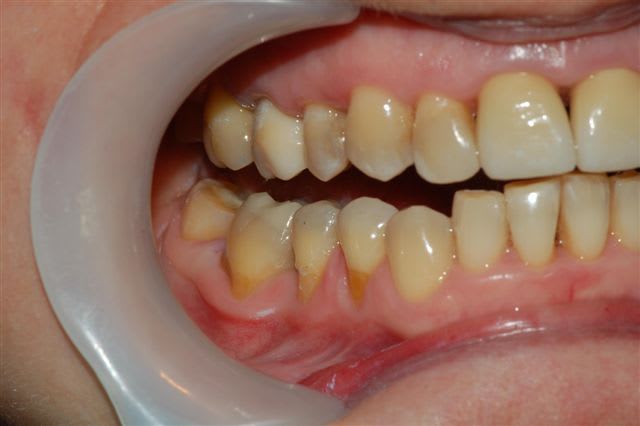

voici un cas traité en dentisterie globale à l'aide du laser en paro et du cerec en occluso, le cas à été terminé en 2010, cette semaine examen microbiologique de routine avec maintenance paro, il n'y a plus de flore pathologique dans la bouche de cette patiente

Emma